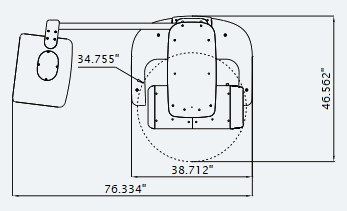

| Without CEPH unit | With CEPH unit | |

| TOP VIEW |

|

|